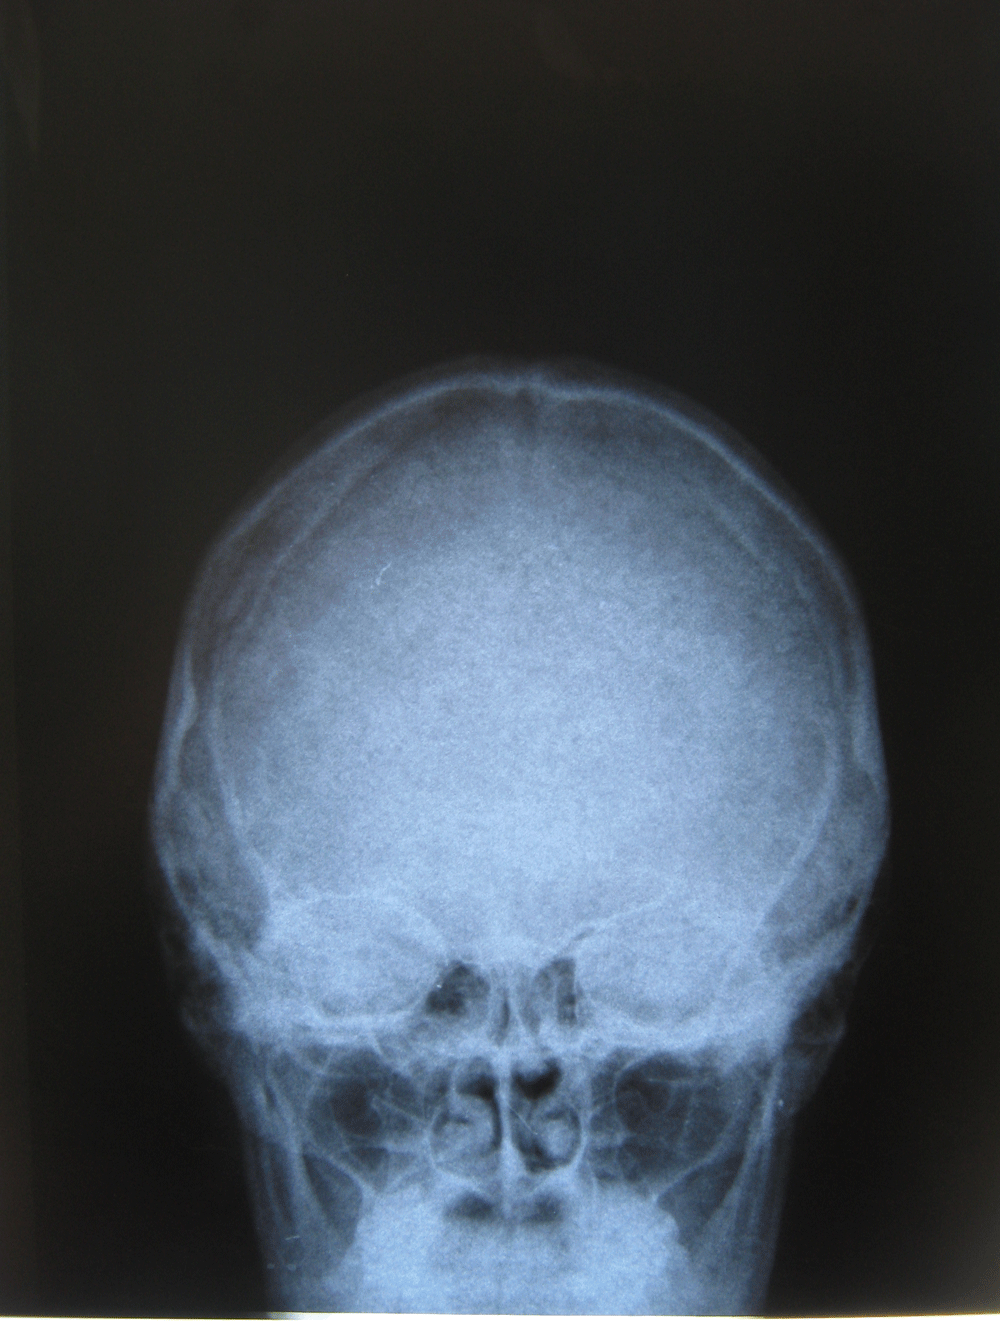

Здравствуйте! Меня сбил автомобиль. Бригада скорой помощи доставила меня в стационар с диагнозом - сотрясение мозга, ушиб грудного отдела позвоночника, компрессионный перелом грудного отдела позвоночника. При поступлении в стационар мне было сделано несколько рентгеновских снимков и поставлен диагноз - компрессионный перелом 4 грудного позвонка. Из-за "мутных" рентгеновских снимков через 9 дней мне сделали КТ и диагноз сняли на основании этого заключения.Судебная медицина - Прикрепленное изображение Мне сказали что перелом шейного позвонка у меня старый и поменяли диагноз - ушиб верхне-грудного отдела позвоночника, болевой синдром. По запросу я получила копию записи КТ. Всю запись КТ выложить не могу, т.к. не могу убрать фамилию. Выкладываю некоторые снимки: Судебная медицина - Прикрепленное изображение Судебная медицина - Прикрепленное изображение Судебная медицина - Прикрепленное изображение Судебная медицина - Прикрепленное изображение Судебная медицина - Прикрепленное изображение Судебная медицина - Прикрепленное изображение Судебная медицина - Прикрепленное изображение Действительно ли по этим снимкам можно сказать, что перелом шейного позвонка "старый"? Правильно ли описание КТ? Я не эксперт, но по-моему 5 грудной позвонок тоже поврежден. Можно ли оспорить заключение врача делавшего КТ? Если можно, то как это сделать? Ведь речь идет об установлении причинно-следственной связи между ДТП и травмой, а до ДТП у меня никаких травм позвоночника не было. Может рентгеновские снимки тоже о чем то скажут.Судебная медицина - Прикрепленное изображениеСудебная медицина - Прикрепленное изображениеСудебная медицина - Прикрепленное изображение